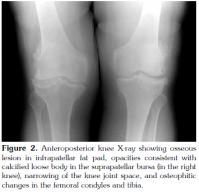

In the physical examination, the patient had an incision scar on the right knee. A difference of 5 cm was found in the right calf compared to the left calf. The right quadriceps muscle had an atrophic appearance. Palpation revealed no effusion. Active flexion of the right knee joint was limited to 110 degrees, and the end of the movement was painful. The right knee joint was capable of full active extension. Bilateral crepitations were present. Anteroposterior view of the X-ray scan showed joint space narrowing and coarse osteophytic formations predominately involving the medial compartment (Figure 1). A right lateral radiograph revealed opacity in the suprapatellar region and an ossific focus measuring 2.25 cm on the longitudinal axis and 2.75 cm on the horizontal axis, located in IFP (Figure 2). Magnetic resonance imaging (MRI) of the right knee showed increased fluid in the suprapatellar bursa and joint. There were loose body formations in the suprapatellar bursa and joint, and a smooth contoured lesion that was hypointense to muscle in the IFP (Figure 3). Routine biochemistry tests showed no abnormalities. The erythrocyte sedimentation rate was 43 mm/h, considered normal for the patient's age. Based on her medical history, physical examination and imaging findings, the patient was evaluated to have advanced Hoffa's disease developing secondary to past trauma or surgery, considering also the ossific focus later forming in the IFP region. Orthopedic consultation was requested. Surgery was recommended. However, medical treatment and physical therapy program was initiated for longterm monitoring, as since the patient did not have severe symptoms and did not consent to surgery. In the course of time, the patient's symptoms relieved.